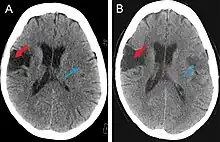

Scanning techniques include EEG, SPECT, MRI, and CT brain scanning.[1][2] These additional techniques are useful in determining what type of lesion the patient has, and allows physicians to determine more effective ways in treating the patient.

CT scan

This computer-tomography type of imaging is one of the most used in any clinical environment and although it can detect some of the brain areas affected by a stroke or a trauma it does not provide the same acuity as the magnetic resonance imaging. CT scans can also reveal, in patients with the syndrome, the bilateral cortical infarcts located in the posterior frontal region involving the opercular areas.[3]